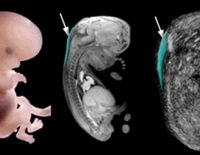

Đo độ mờ da gáy là gì và ý nghĩa khi thực hiện trong thai kỳ

Một trong những kiểm tra cần thiết trong thai kỳ mẹ cần thực hiện là đo độ mờ da gáy. Việc đánh giá thai nhi có nguy cơ bị bệnh Down hay không chính là nhờ vào phương pháp này. Tuy nhiên, tính chính xác...